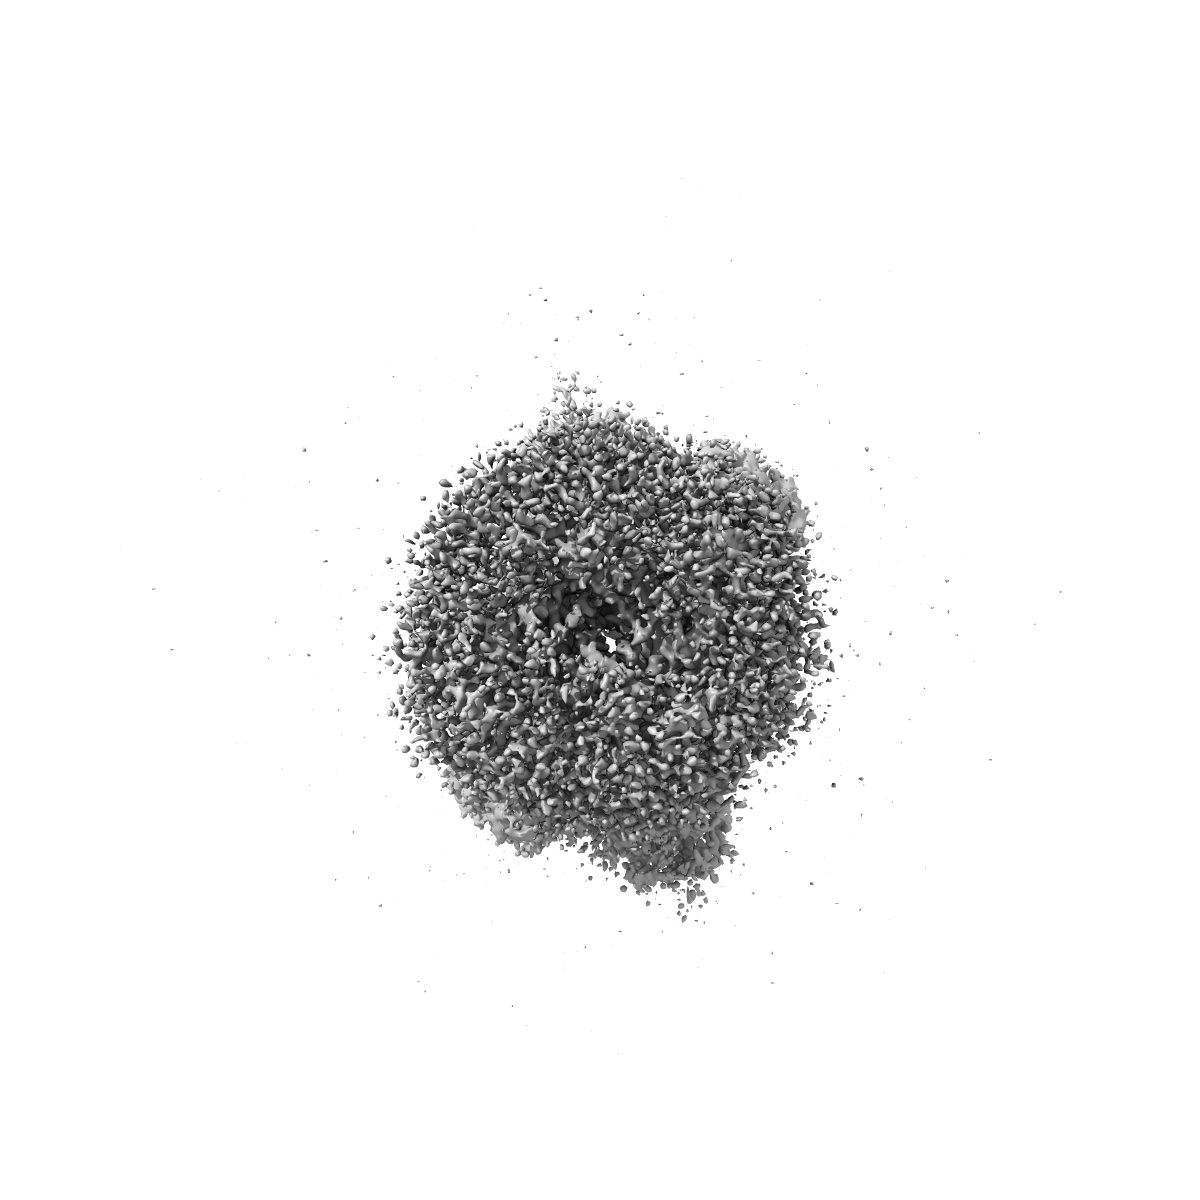

Glycine and glutamate bound GluN1a-GluN2B NMDA receptors in non-active 1 conformation at 2.97 Angstrom resolution

Single-particle

2.97 Å

Sample Organism: Rattus norvegicus

Sample: Hetero-tetrameric GluN1a-GluN2B NMDA receptors

Fitted models: 7saa